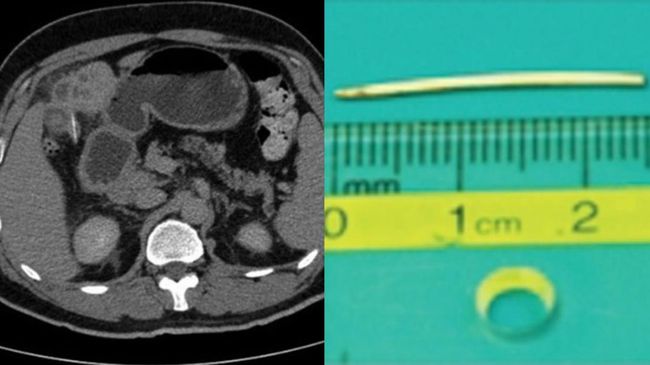

Foto: Liver rusak parah pada pasien yang tak sengaja tertelan tulang ikan. (National Library of Medicine)

Dalam laporan yang dipublikasikan di National Library of Medicine, tim dokter menemukan ada dua kelainan pada bagian tengah liver pasien. Salah satunya adalah lesi yang tampak seperti abses, dan yang lainnya adalah benda padat seperti ranting di dalam lesi tersebut yang berukuran sekitar 2,5 cm.

Setelah pasien diberikan antibiotik, dokter melakukan operasi perut yang disebut laparotomi untuk mengeluarkan benda asing tersebut. Ternyata itu adalah tulang ikan.